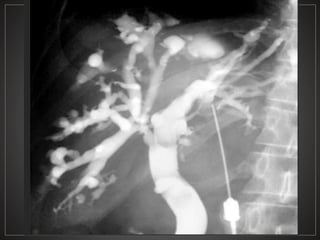

ENF. DE CAROLI:Dilatación sacular CONGENITA y segmentaria de los CBIH SX. DE CAROLI: Dilatación del conducto cístico+ Fibrosis hepática.

• 47.

Etiología Tipo simple Malformación de laplaca ductal de los CBIH centrales amplios Adultos jovenes Tipo fibrosis periportal Asocia a ectasia tubular, fibrosis y enfermedad poliquistica. Lactantes y niños TIPO CONGENIT A autosómica recesiva

• 48.

CPRE: Dilataciones saculares de CBIH. TC: Simple:Áreas redondas, hipointensas en topografía de CBIH. Contraste: Signo del punteado central. RM: T2: Espacios quísticos hiperdensos